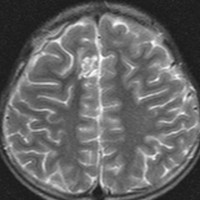

放射線治療がほとんど効かなかった例(高悪性度グリオーマに類似するもの)

手術で簡単にとれそうなPNETです。実際に全摘出していただいて,すぐに脳脊髄照射と腫瘍床照射54グレイの放射線治療を受けたのですが,放射線治療最中に手術摘出した場所から再発してしまいました。再手術で摘出して,シスプラチンを基剤とした併用化学療法やテモゾロマイドを使いましたが,間もなく激しい脳脊髄播種を生じました。MIB-1は70%で,膠芽腫のように強いanaplastyがありました。

放射線治療が最も強力な治療手段なのですが,全く無効なPNETがあります。